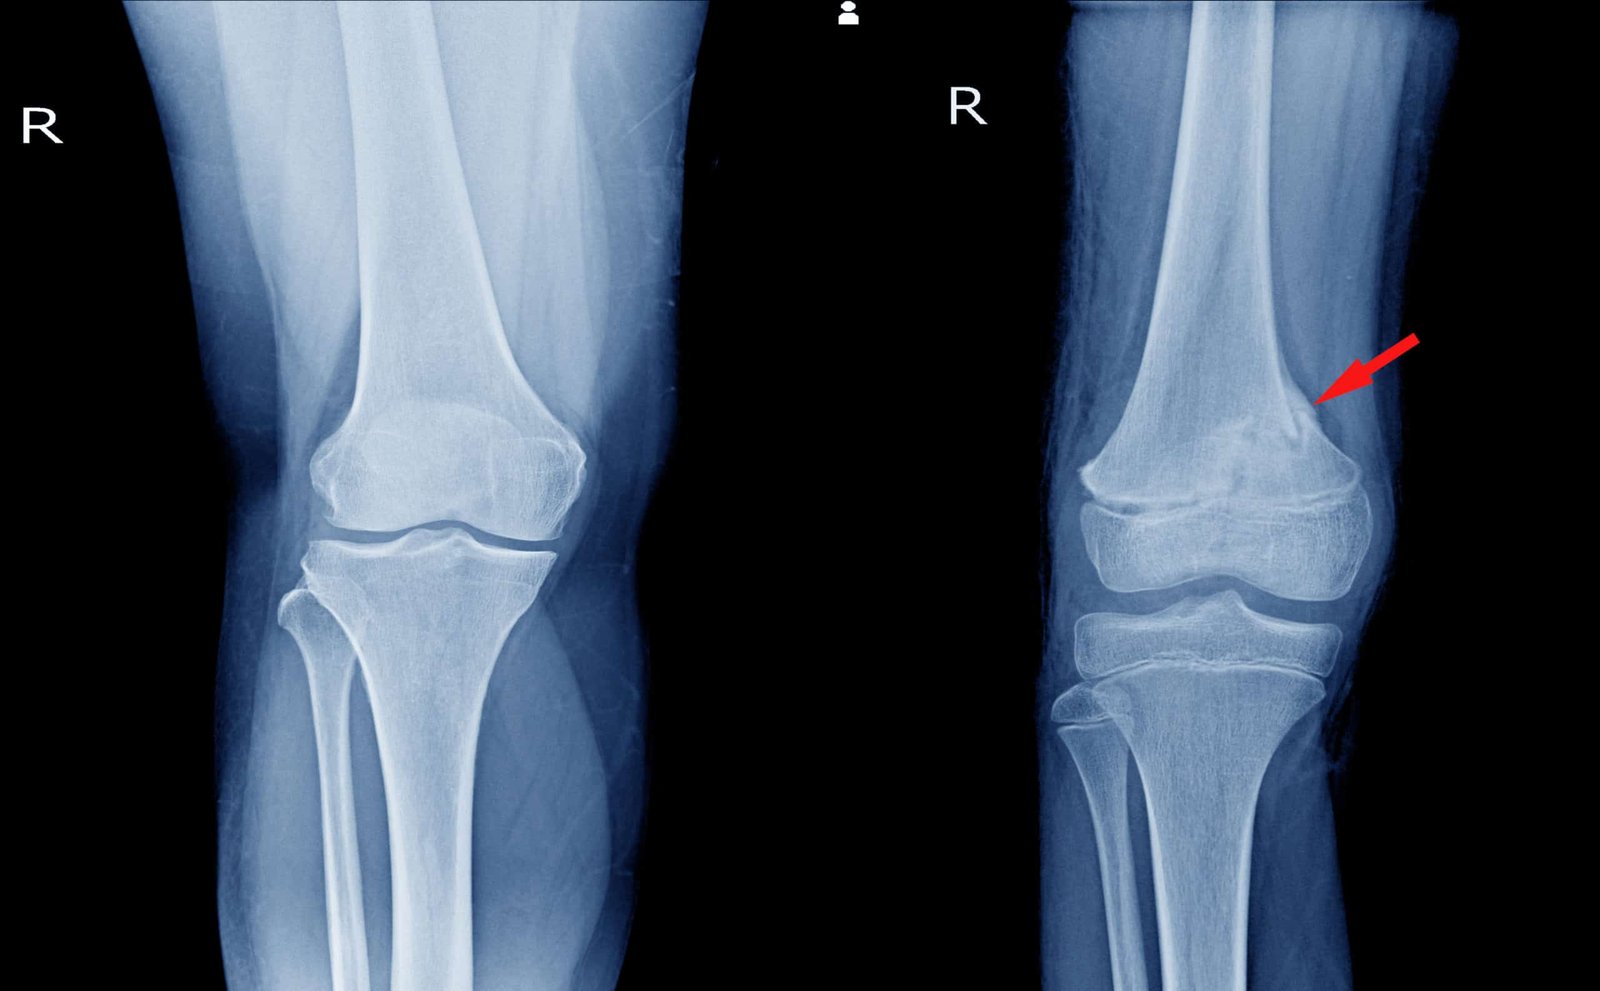

Common fracture of the femur:

1) Proximal femur fractures.

i. Subtrochanteric fracture.

ii. Fracture of neck of femur.

2) Fracture shaft femur.

3) Supracondylar fracture of femur.

4) Ipsilateral fractures of femoral shaft and neck.